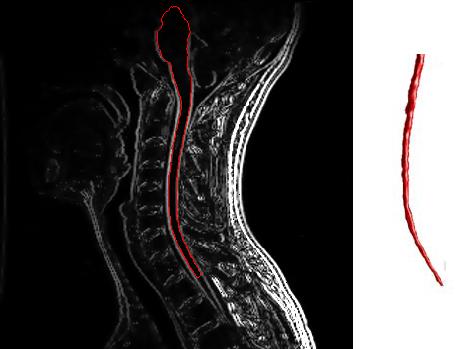

MS is an inflammatory disease in which the protective myelin sheathing that coats nerve fibers in the brain and spinal cord is damaged and ultimately stripped away – a process known as demyelination. During the highly variable course of the disease, a wide range of cognitive, debilitating and painful neurological symptoms can result.

Image Source: The cervical spine MRI with enhancement showing areas affected by MS image is credited to the United States Department of Health and Human Services and is in the public domain.